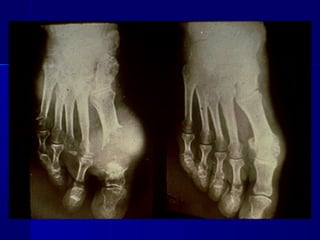

GOTAGOTA

 Presenta las siguientes manifestaciones:Presenta las siguientes manifestaciones:

1.1. HiperuricemiaHiperuricemia

2.2. Crisis de artritis aguda por depósito deCrisis de artritis aguda por depósito de

cristales de urato.cristales de urato.

3.3. Eventual desarrollo de artritis y gota tofáceaEventual desarrollo de artritis y gota tofácea

crónicacrónica

4.4. Intervalos asintomáticos entre las crisisIntervalos asintomáticos entre las crisis

Correlación clínicaCorrelación clínica

 En el 50 % de los primeros ataques de artritis seEn el 50 % de los primeros ataques de artritis se

afecta el I dedo del pie, que se produce después deafecta el I dedo del pie, que se produce después de

una ingesta excesiva de comida o exceso de alcohol.una ingesta excesiva de comida o exceso de alcohol.

 El primer ataque remite espontáneamente, luego seEl primer ataque remite espontáneamente, luego se

afectan otras articulaciones y aparece la artritisafectan otras articulaciones y aparece la artritis

gotosa crónica, que presentan cierto deterioro de lagotosa crónica, que presentan cierto deterioro de la

función renal.función renal.

 Los fármacos úricosuricos son eficaces para controlarLos fármacos úricosuricos son eficaces para controlar

la gotala gota